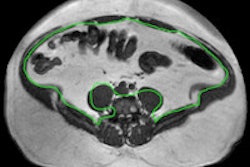

In other findings, the researchers found that nearly 2.3 million people in the U.K. were living with some form of coronary heart disease in 2012, including approximately half a million with heart failure and 1.1 million with atrial fibrillation.

England was found to have the lowest prevalence of all cardiovascular conditions of the four U.K. countries. Regional variations were noticeable, however, with higher rates found in the north of England than in the south, according to the researchers. The group found that Scotland had the highest prevalence of coronary heart disease, stroke, and peripheral vascular disease. Wales had the highest prevalence of high blood pressure, heart failure, and atrial fibrillation.